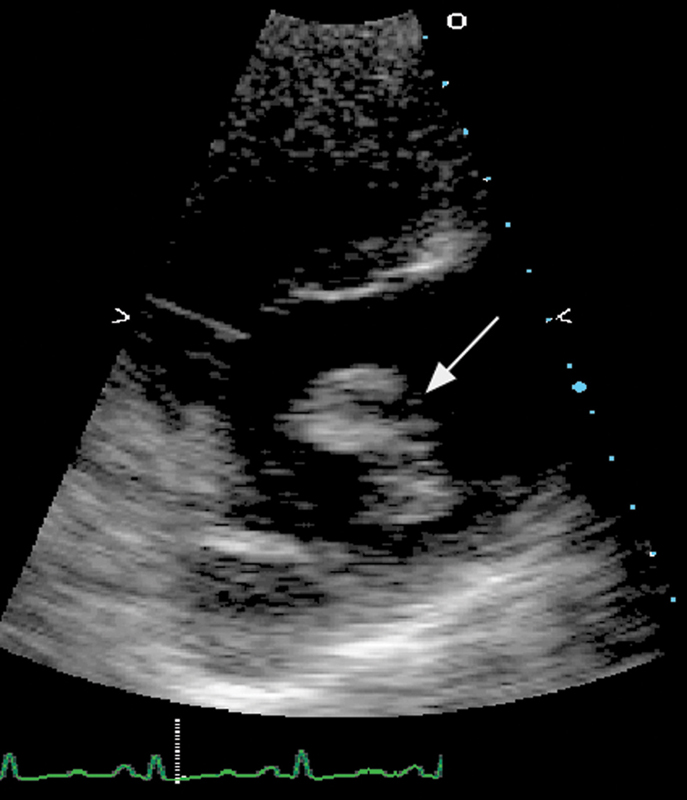

فحوصات تشخيصية لبعض امراض القلب والشرايين التاجية